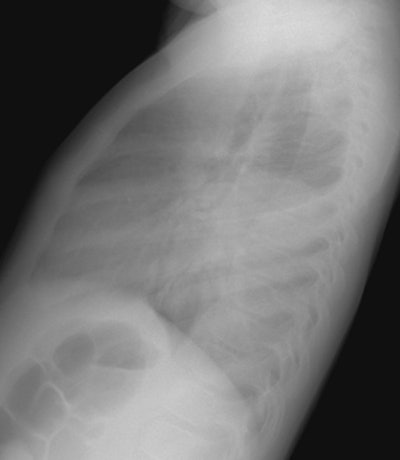

The CXR demonstrates a large left lung mass. The patient was initially felt to have a pneumonia, but subtle rib destruction can be seen involving the left posterior ninth rib. When the radiographic findings did not improve a CT scan was performed (See below). (Click images to enlarge)